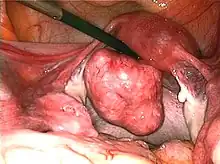

Uterine fibroids as seen during laparoscopic surgery

Treatment of an intramural fibroid by laparoscopic surgery

After treatment of an intramural fibroid by laparoscopic surgery

Myomectomy is a surgery to remove one or more fibroids. It is usually recommended when more conservative treatment options fail for women who want fertility preserving surgery or who want to retain the uterus.[62]

• A laparoscopic myomectomy is done through a small incision near the navel. The physician uses a laparoscope and surgical instruments to remove the fibroids. Studies have suggested that laparoscopic myomectomy leads to lower morbidity rates and faster recovery than does laparotomic myomectomy.[63]